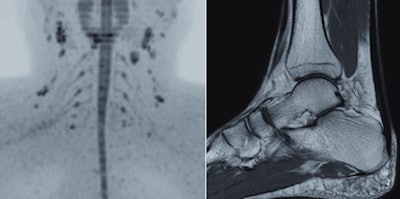

Expanding on its global R&D footprint that includes a new high-tech facility in Suzhou, China, Philips has developed a reliable and simple to use machine for developing markets. The Multiva 1.5-tesla unit is designed to ease patient discomfort and increase productivity by reducing the time spent setting up an examination. It features the FlexStream workflow system, which enables efficient handling of coils for head, spine, musculoskeletal, and neurovascular examinations, allowing a reduction of up to 40% in the time it takes to position the patient and coils before securing an image, according to the manufacturer.

Another feature of the Multiva system is SmartSelect software, which automatically determines which coils and elements should be activated to yield the maximum SNR in the region of interest for greater efficiency and higher image resolution. Additionally, a large neurovascular coil design allows patients to use headphones during their examination, which can help improve patient comfort. These improvements will maximize the value of the system and allow clinicians to treat more patients each day without compromising image quality, the company explained.